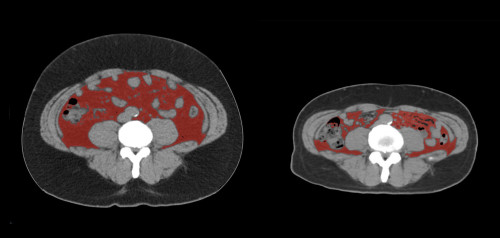

③

50代・男性(ご本人のご厚意で画像提供)

治療内容:チルゼパチド5.0mgの週1回自己注射による脂肪減少と脂肪肝改善

治療期間: 6ヶ月(26週)((用量は2.5mgから開始し最大で15mg。減量効果が得られる必要用量には個人差があります。))

費用:自由診療の場合は7700円(税込)×26(週)=200200円

想定されるリスク・副作用:下記に副作用を記載

※医療広告ガイドラインに準拠して表記

1:脂肪の減少

皮下脂肪の減少(赤色部分)